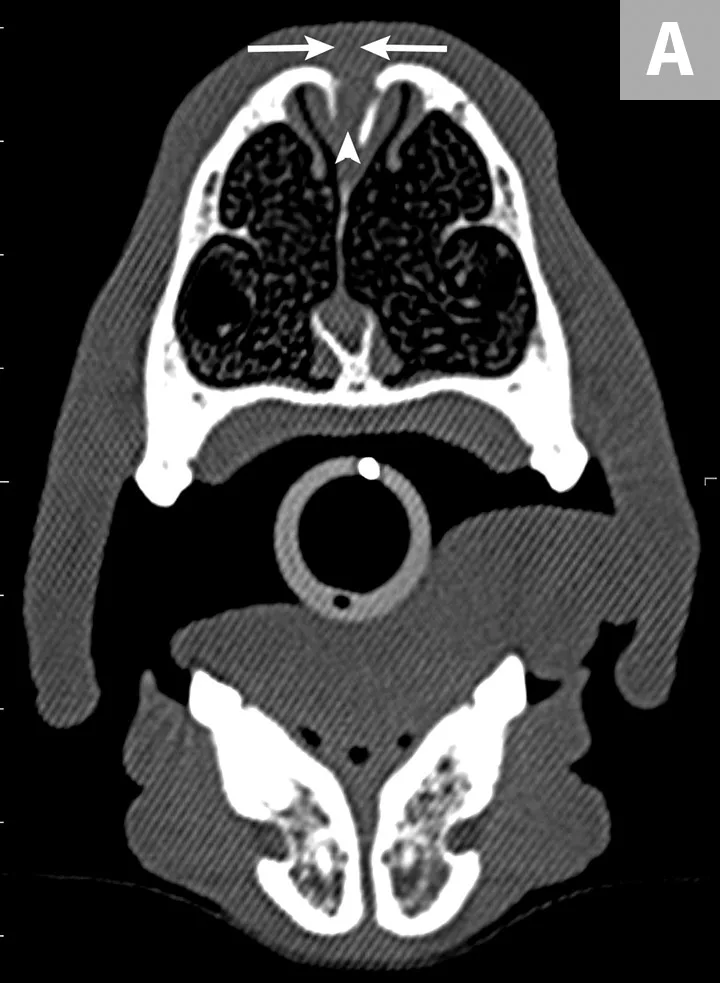

FIGURE 2A

Precontrast, transverse plane CT image of the nasal passages at the level of the second premolars (A). There is an absence of complete closure of the nasal bone suture (arrows) and dilation of the most dorsal aspect of the nasal septal wall with soft tissue density (arrowhead). Precontrast, transverse plane CT image of the nasal passages at the level of the third premolars (B).